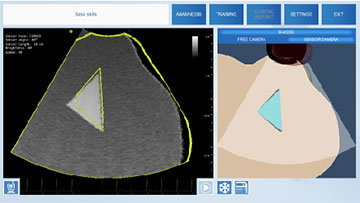

Виртуальный симулятор ультразвуковых исследований (УЗИ) SonoVision – обучающий тренажер на единой платформе обеспечивающий освоение основных навыков проведения ультразвукового исследования, понимание и идентификацию различных заболеваний и патологии внутренних органов человека.

SonoVision – симулятор ультразвуковой диагностики является инструментом для профессионального изучения медицины. Это виртуальный симулятор для отработки навыков ультразвуковой диагностики. Он используется как студентами, так и практикующими специалистами в клиниках и больницах. Симулятор ультразвуковой диагностики – прекрасное дополнение к традиционному обучению и повышению квалификации медицинского персонала.

Новое поколения симулятора УЗИ гарантирует высочайший уровень детализации внутренних органов, а работа с анатомически корректным манекеном обеспечивает реалистичные тактильные ощущения и визуальную картину при выполнении вмешательств. В симуляторе реализовано более 40 клинических сценариев.

Использование реалистичных имитаторов датчиков ультразвукового исследования.

- Трехмерная модель органов в окне виртуальной реальности;

- Отслеживание положения датчика УЗИ в режиме реального времени;

- Измерения органов и настройка параметров УЗИ изображения.

Важными элементами симулятора являются анатомически корректный фантом торса пациента и аналогичный реальному датчик УЗИ.